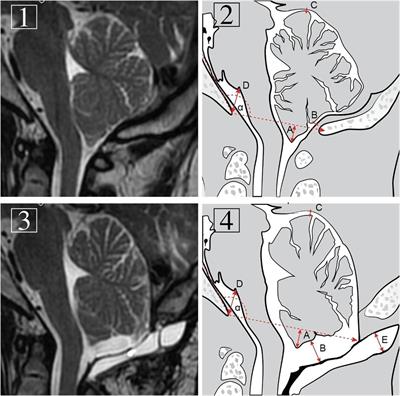

Significance of Pseudomeningocele After Decompressive Surgery for Chiari I Malformation